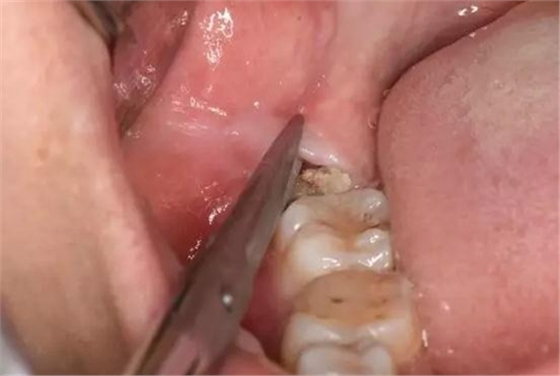

圖6. 剪刀做遠中小切口、暴露遠中邊緣嵴